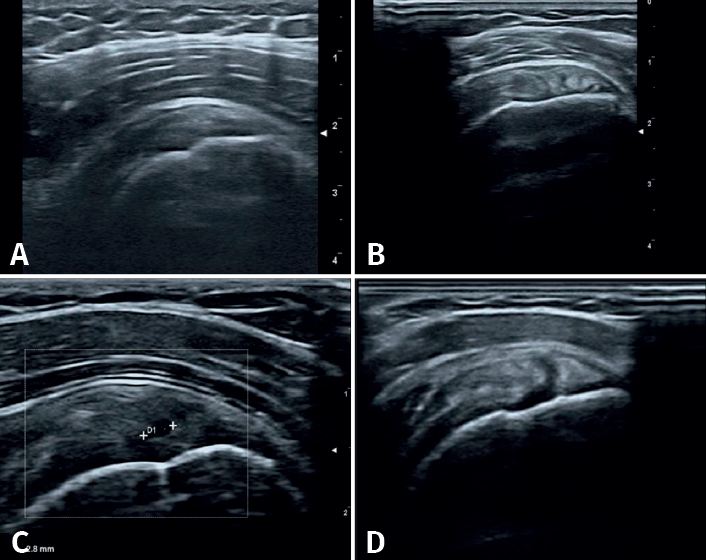

Se definieron los diagnósticos ecográficos de la siguiente manera (Figura 2): 1) tendinopatía: alteración de la ecoestructura fibrilar con alternancia de imágenes hiper- e hipoecogénicas a pesar de la corrección de la anisotropía con movimientos del transductor; 2) rotura tendinosa: imagen anecogénica intratendinosa que puede incluir a la rotura parcial (de tamaño variable con interrupción parcial de la ecoestructura normal), la rotura parcial del espesor completo (la cual abarca el espesor tendinoso en su totalidad) y la rotura completa (en la que se observa discontinuidad del tendón, generalmente presentándose adelgazado y en ocasiones con retracción tendinosa). Otras lesiones: la bursitis se observa como imagen anecogénica de más de 2 mm de grosor, localizada o generalizada entre en tendón del supraespinoso por abajo y el músculo deltoides por arriba o el borde lateral del troquíter; la artrosis acromioclavicular se caracteriza por irregularidades de sus perfiles corticales con la presencia de osteofitos y distensión de la cápsula; la rotura de labrum posterior con discontinuidad dada por una imagen hipoecoica en el borde de este; y la tendinopatía calcificante: imagen hiperecogénica sólida, única o múltiple, de tamaño variable, con o sin sombra posterior(6)(Figura 3).